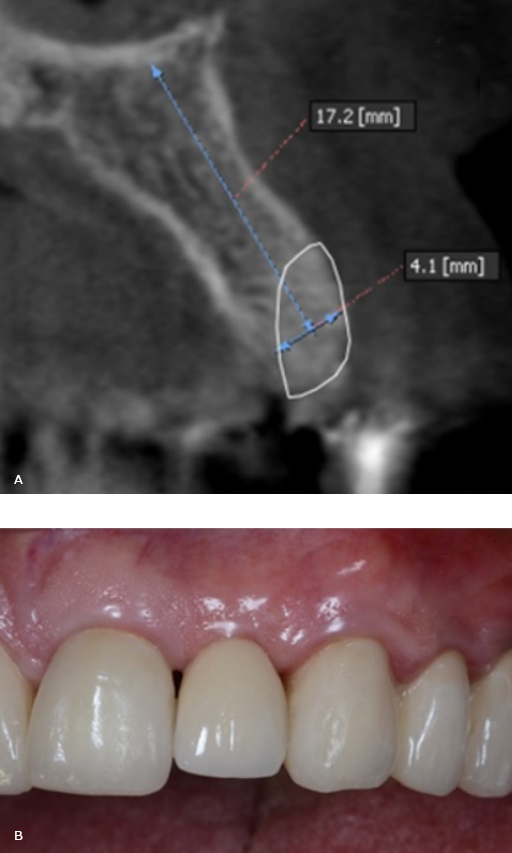

62-year-old male patient, with stands for American Society of Anesthesiologists Classification 2 and arterial hypertension medicated with Enalapril 20 mg/day, partially dentate. The radiographic exam showed the presence of advanced buccal bone resorption in relation to the maxillary left lateral incisor (Tooth 2.2). It was a result of the root displacement secondary to root fracture (Fig. 1, A). The patient’s main complaint was aesthetic.

Fig. 1 - A: Cone Beam Computer Tomography (CBCT) images tooth 2.2. B: Tooth extracted using an atraumatic periotome technique. C: Root and crown extracted. D: A resorbable collagen membrane was adapted to the bone defect and placed in position to recreate the buccal plate.

Four months after grafting the extraction site in preparation for dental implant placement, conventional radiology and CBCT showed an adequate height and width of the bone (Fig. 3, A).

In a second surgical phase, one implant was placed (Screw-Vent, Zimmer Biomet Dental) (3.3 x 16 mm) with an average surgical torque of 35 Ncm. Six months after the implant placement was radiographically controlled, osseointegration was clinically confirmed and a provisional crown screwed on the implant was performed. After several stages, the final restoration with a zirconium dioxide abutment and a full ceramic crown was obtained and cemented (Fig. 3, B).

Fig. 3 - A: Four months after grafting the extraction site in preparation for dental implant placement, conventional radiology and CBCT showed an adequate height and width of the bone. B: Final restoration with a zirconium dioxide abutment and a full ceramic crown.